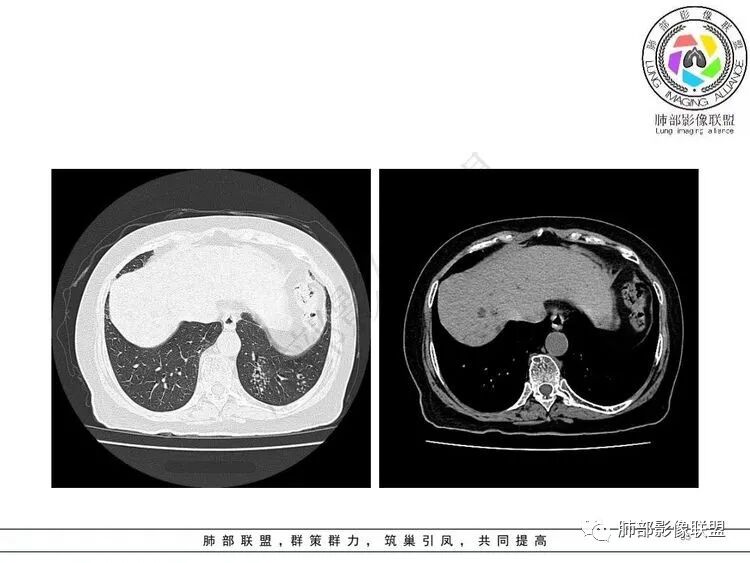

2.纵隔左移。肺动脉增宽。

3.左肺上叶较大范围实性密度区,密度偏高不均,支气管穿行且轻度扩张,可见无壁不规则空洞(未能显示外壁),未显示液平或腔内结节。

4.左肺下叶多发结节影及条索影,密度不均,边界较清楚,可见树芽征。

5.纵隔见轻度增大淋巴结,较密实。

1.左肺上叶较大范围实性密度区,支气管未见阻塞,无壁空洞,整体比较“干”,加之纵隔左移,比较符合病程较长的结核性病变。

左肺下叶多发结节影、条索影、树芽征等具有相当明显的提示意义—符合继发性肺结核。